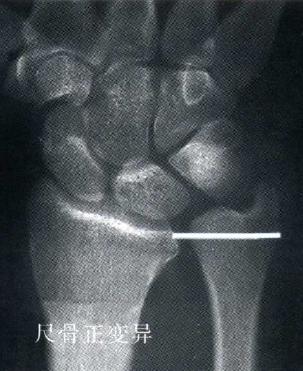

·诊断性放射检查包括:腕关节平片、旋转中立位的后前位片及侧位片。

·这能让术者评估骨折、通过腕骨排列不齐判断韧带不稳以及尺骨变异。判断尺骨变异非常重要,因为它将影响治疗方法的选择。